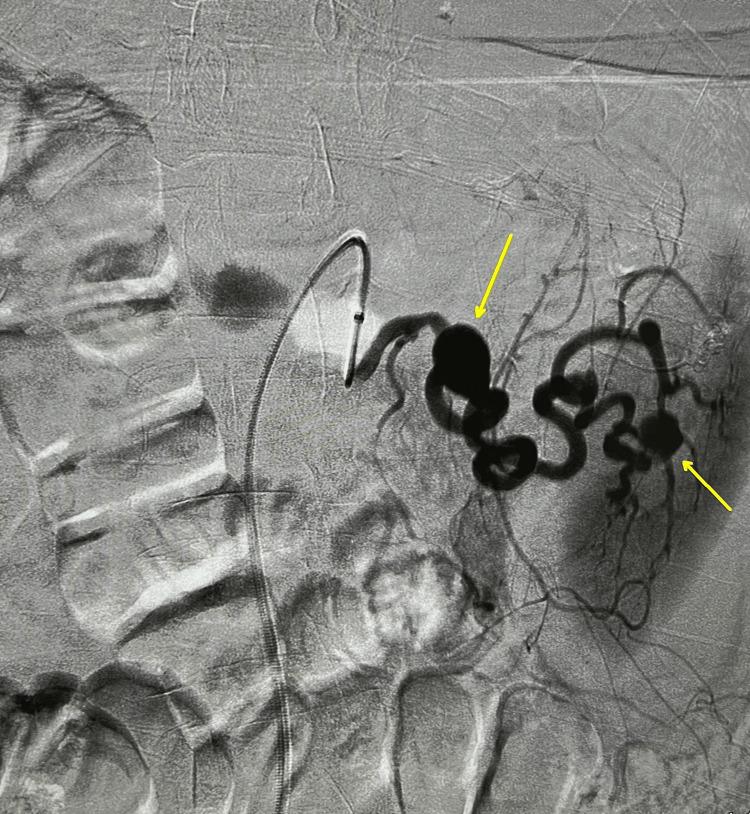

Patients presenting with ascites should be properly evaluated to differentiate potential etiologies. Then, based on the evaluation, we can tailor more accurate treatment plans for patients. Cirrhosis is the most common cause, and others include cancer, heart failure, and, in our case, rarely a visceral artery rupture. Rupture of the splenic artery aneurysm can be lethal and should be considered as a possible differential in a patient with no previous history of heart failure, cancer, or cirrhosis. Our patient was identified after an initial misdiagnosis of possible ascites secondary to cirrhosis. However, input from an interventional radiologist led to proper identification and tailored management. Early treatment is crucial to prevent complications, including death.